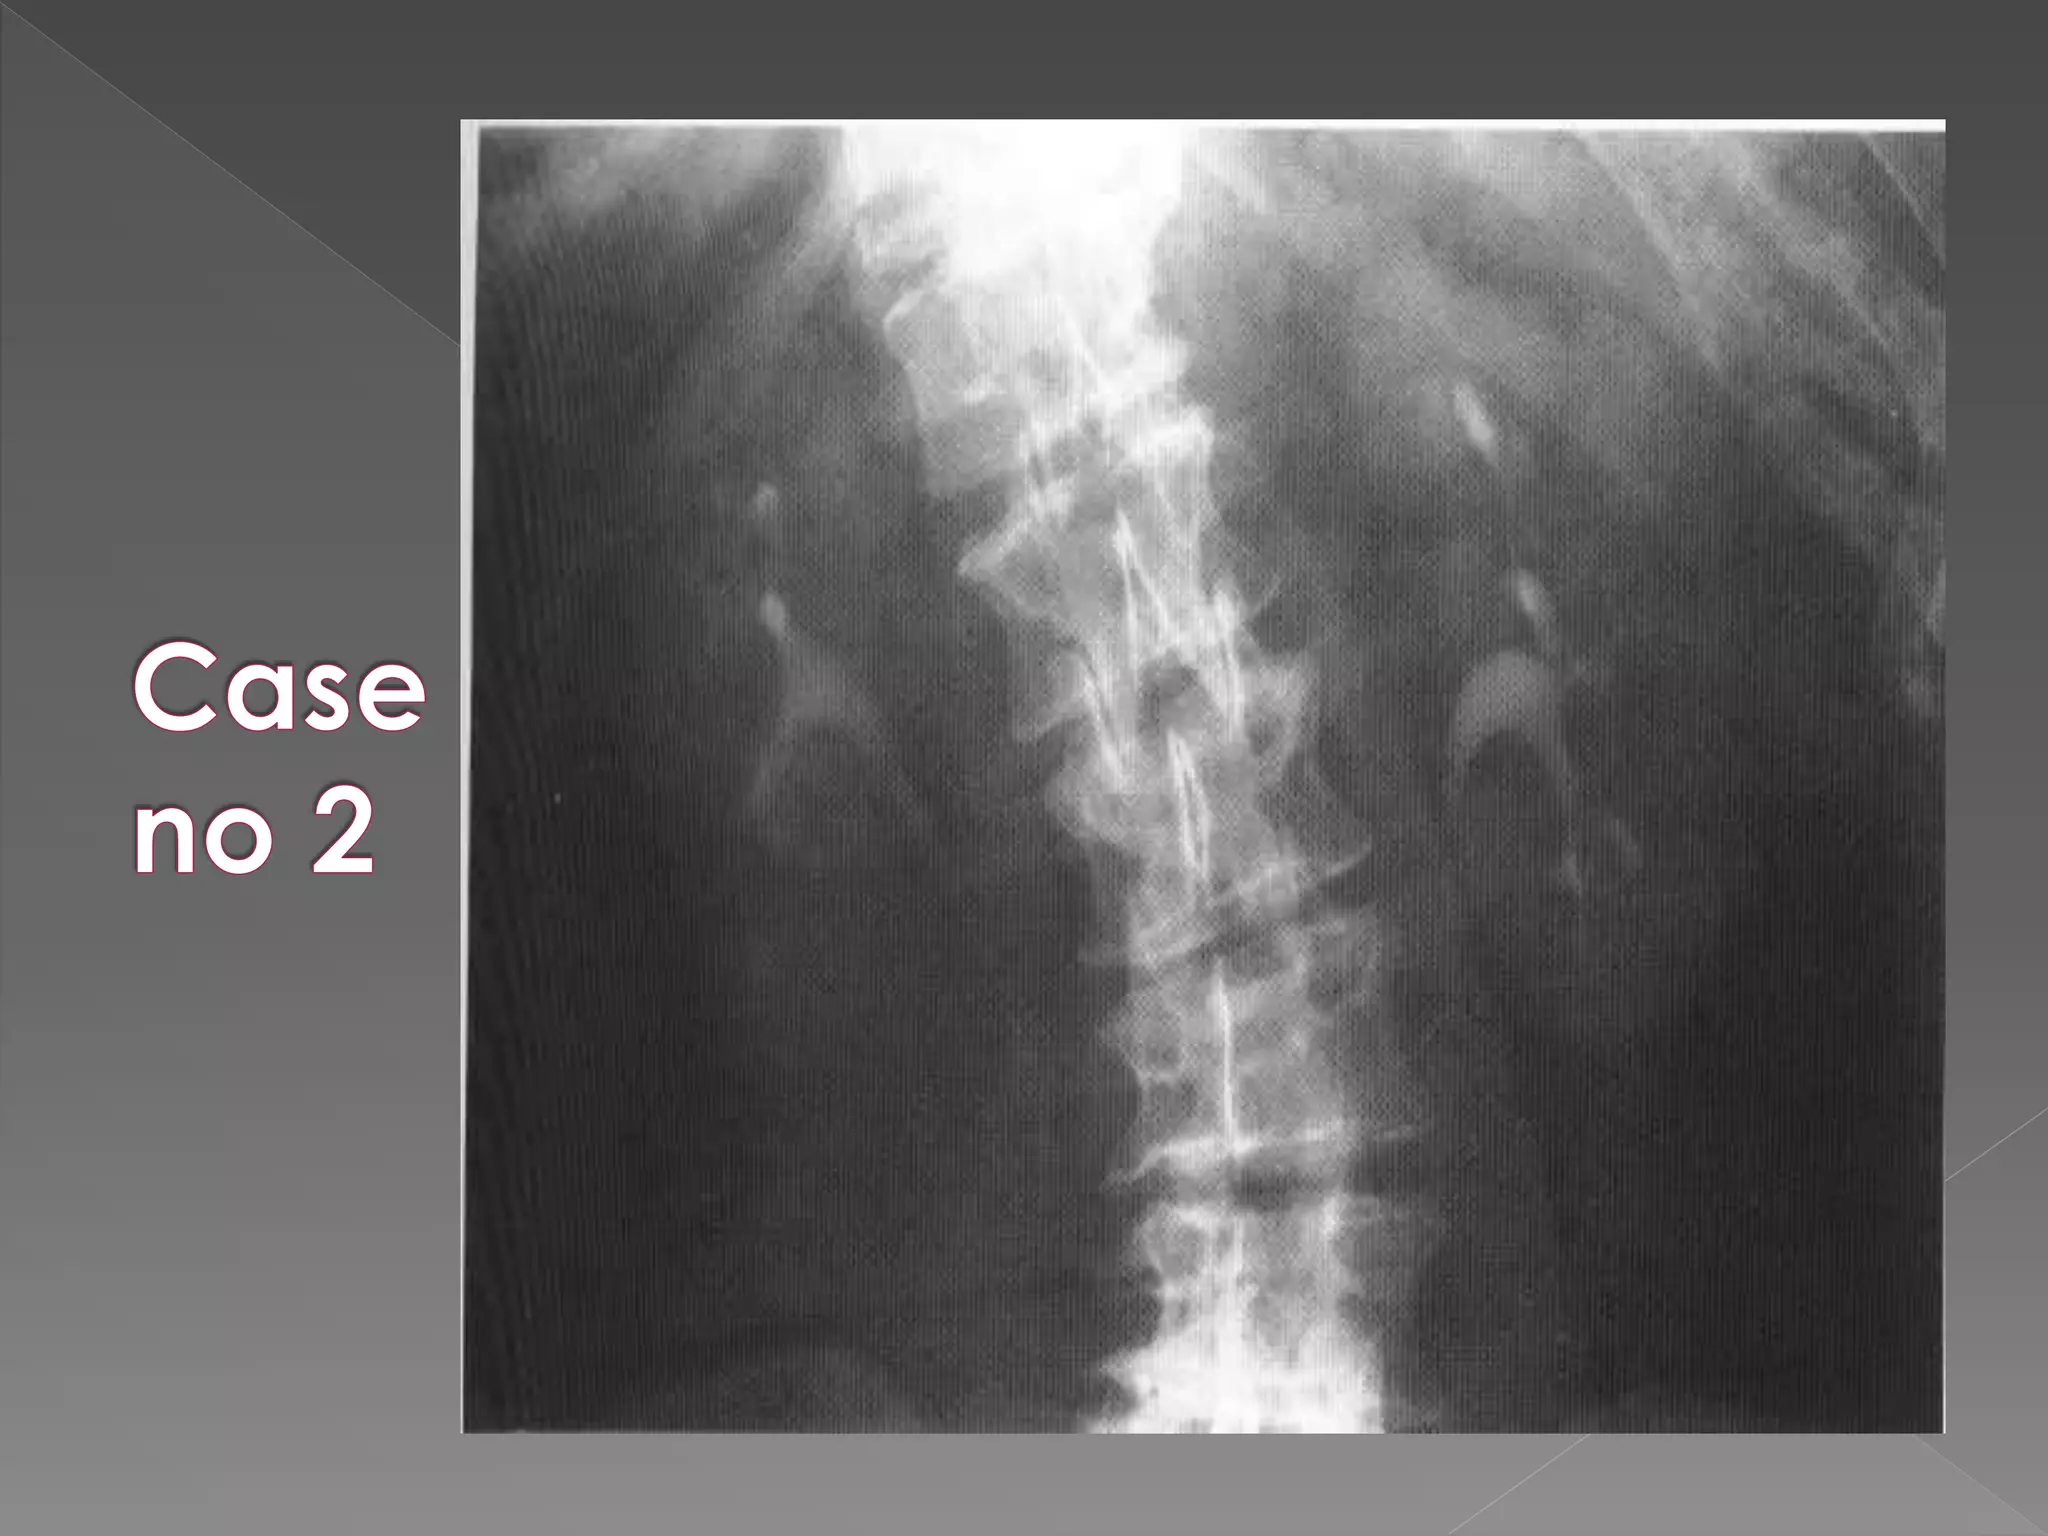

 The plainfilm demonstrates calcification within distended upper pole calyces